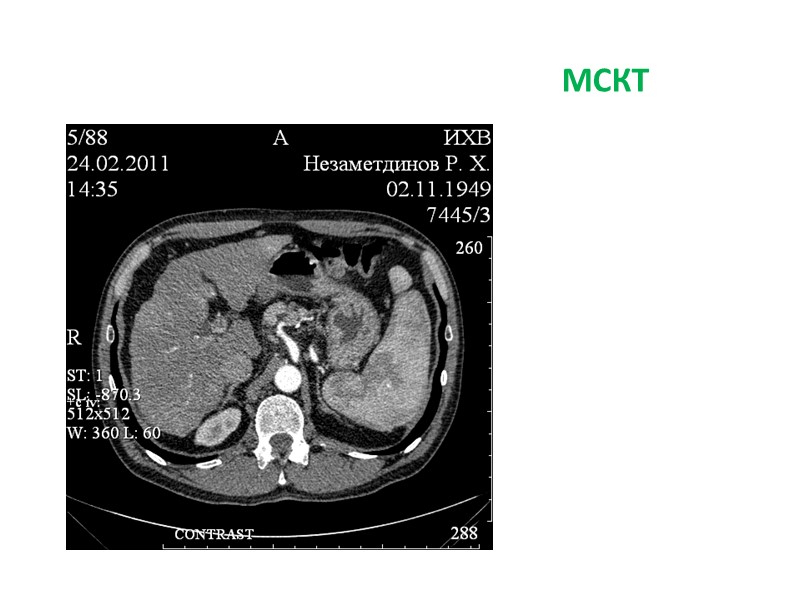

Больной В., 50 лет Диагноз: первичный рак правой доли печени (холангиоцеллюлярный?) с метастазами в левую долю T3N0-1M1. Состояние после портоэмболизации правой доли печени 26.01.2011. МКБ Хронический пиелонефрит. Микролиты обеих почек.

МСКТ